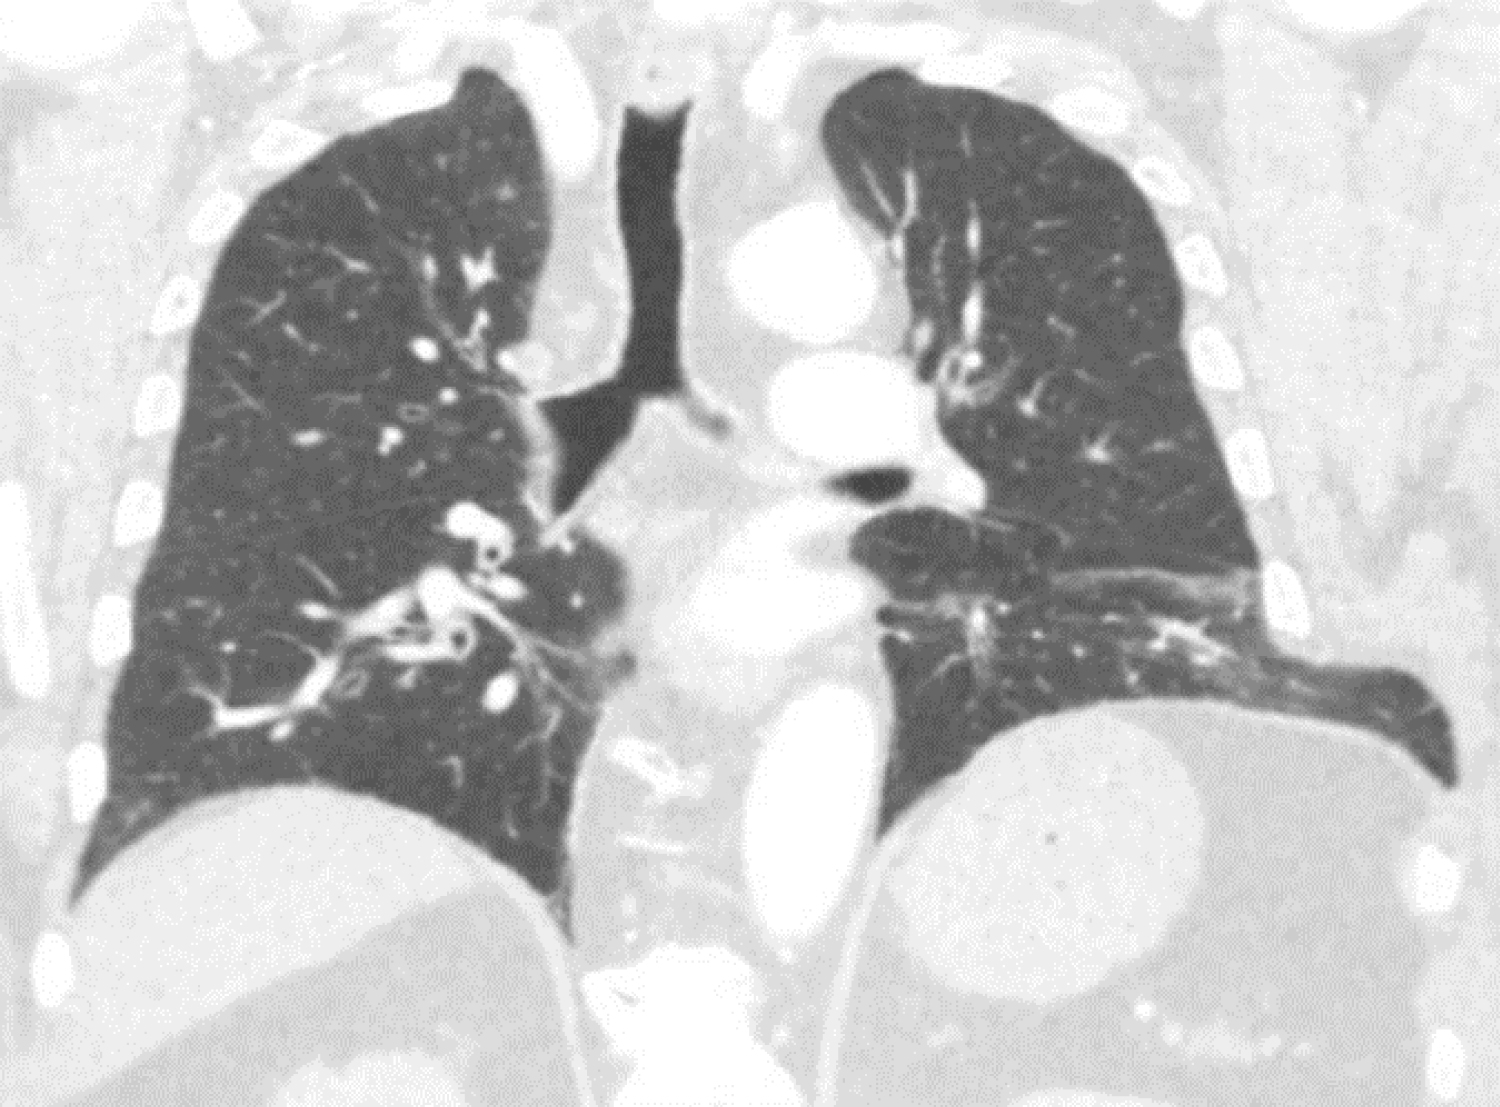

A 54-year-old male with a history of heavy smoking and morbid obesity presented at the clinic with pain and a palpable mass in the right thoracic wall. Anamnesis revealed no recent trauma, but the patient was involved in an accident four years ago, falling down from considerable height. Having little complaints he never visited a doctor. Years later, after having to sneeze multiple times the patient heard a clear cracking sound originating from his right thorax. However, since he did not experience any pain or symptoms he neglected again to consult with a physician. Not long after, following significant weight loss, the patient noticed a painful mass on the right side of his thorax. During the physical examination a palpable bulge with a positive Valsalva maneuver was found. Plain X-ray showed rib fractures with callus formation of the 7th, 8th and 9th ribs on the right side, no evident pulmonary abnormalities were noted. A CT-scan was made revealing consolidated fractures of ribs 7 till 9 on the right side with herniation of lung tissue between ribs 7 and 8 (Figure 3). After careful consideration, taking into account the symptoms, size of the herniation and subsequent deformity of the thorax, the patient was planned for surgery. During the procedure multiple consolidated rib fractures were seen with secondary malalignment of the ribs. Between ribs 8 and 9 there was a tear of the intercostal musculature which created a defect where lung tissue protruded. The 8th and 9th were reconstructed with a rib plate and in the intermediate intercostal space a polypropylene mesh was placed. The first weeks of recovery were uneventful, though three weeks after surgery the patient returned to the clinic because of swelling around the site of the operation. Ultrasound revealed a large fluid collection, which after drainage turned out to be a seroma. There was no sign of infection and the patient recovered without any more complications at one year follow up.

Figure 3: Computed tomogram frontal plane view shows a consolidated rib fracture of the 8th rib on the right side with herniation of lung tissue between ribs 8 and 9. View Figure 3